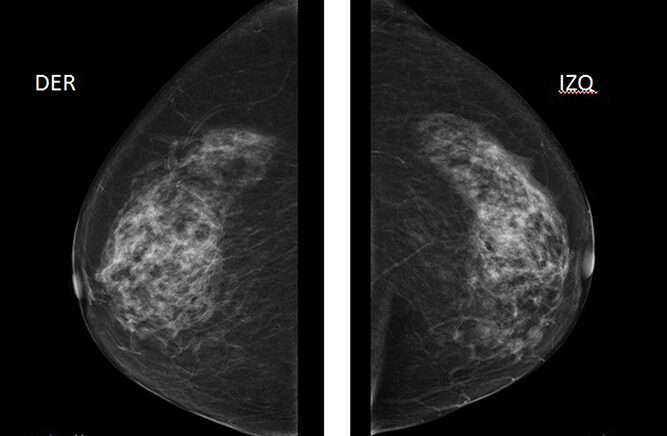

Dado que el cáncer de mama bilateral puede ser un desafío diagnóstico, es crucial que las mujeres que han sido diagnosticadas con cáncer de mama realicen un seguimiento regular para detectar cualquier cáncer oculto en la mama contralateral o en la mama ipsilateral, si ha sido conservada. La mamografía es la herramienta más comúnmente utilizada en estos casos, y debe realizarse antes de iniciar cualquier tratamiento primario para asegurar que no haya un cáncer no detectado en la mama contralateral. Posteriormente, las mamografías deben continuar a intervalos regulares, ya que el riesgo de desarrollar un cáncer en la segunda mama persiste con el tiempo. Este seguimiento regular es esencial para detectar tumores en sus etapas más tempranas y mejorar las perspectivas de tratamiento y supervivencia.